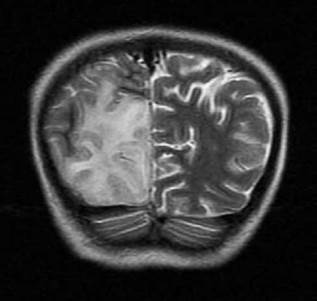

Seis meses después, la paciente presentó deterioro neurológico progresivo, disminución de la fuerza muscular, persistencia de la marcha atáxica, mutismo y falta de seguimiento visual. La TAC de cráneo de control evidenció lesión sugestiva de infarto cerebral en el lóbulo occipital derecho y la RMN en T1 mostró hipointensidad cortico-subcortical temporo-occipital derecha con leve efecto compresivo sobre la línea media y el cuerno occipital del ventrículo lateral ipsilateral (Figura 1), por lo que se sospechó diagnóstico de síndrome MELAS. Se obtuvieron diferentes trazados espectrales del parénquima sano que se correlacionaron con los resultados de la RMN, lo cual permitió observar una disminución en los picos de N acetil aspartato, colina y creatina, y la aparición de pico dominante de lactato cerebral.

Imagen por resonancia magnética cerebral potenciada en T1, corte axial, en la que se observa lesión isquémica a nivel occipital derecho con leve efecto compresivo sobre la línea media y el cuerno occipital del ventrículo lateral del mismo lado.

Figura 1: Imagen por resonancia magnética cerebral potenciada en T1, corte axial, en la que se observa lesión isquémica a nivel occipital derecho con leve efecto compresivo sobre la línea media y el cuerno occipital del ventrículo lateral del mismo lado.

Fuente: Documento obtenido durante la realización del estudio.